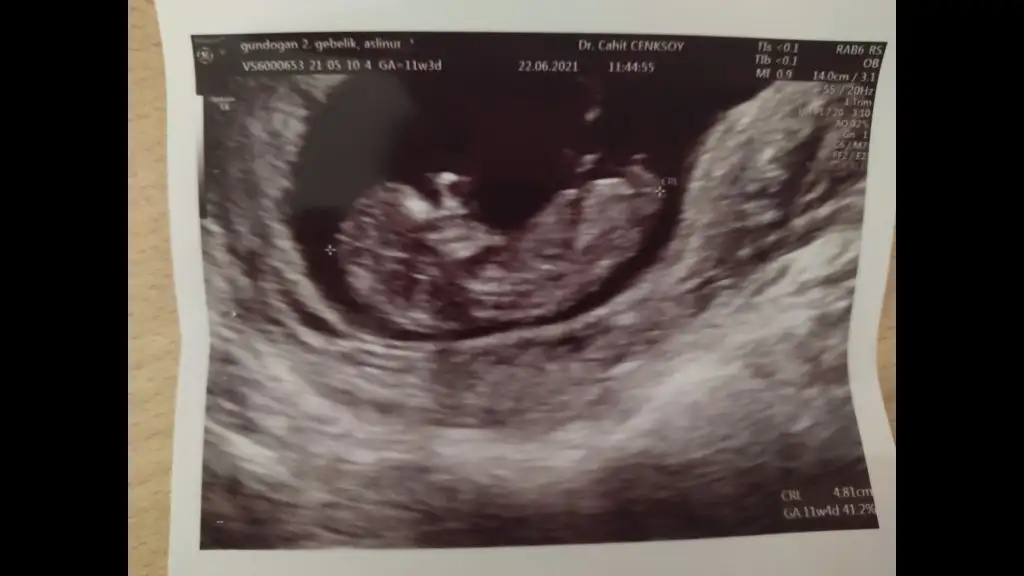

Kız görünüyorMerhabalar bize de bakabilir misiniz rica etsem 12 haftalık Eki Görüntüle 2873057 Eki Görüntüle 2873058